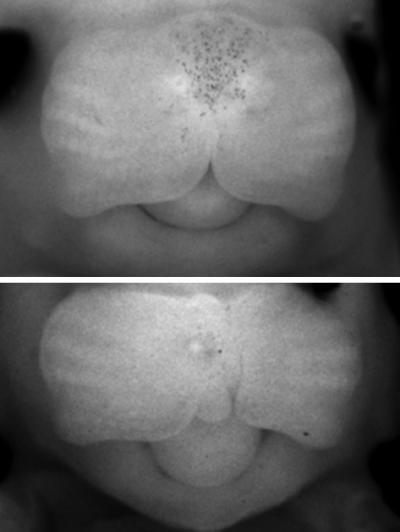

Previous studies had shown that variations in a large stretch of DNA are more frequent in people with cleft lip or cleft palate. But there are no genes in or around this DNA stretch, so it was unclear what its role might be. To answer this question, Spitz and colleagues genetically engineered mice to lack that stretch of DNA, as the mouse and human versions are very similar, and are therefore likely to have the same role in both species. They found that these genetically engineered mice had slight changes to the face – such as a shorter snout – and a few had cleft lips. The scientists also used this mouse model to look at what happened during embryonic development to lead to those changes.